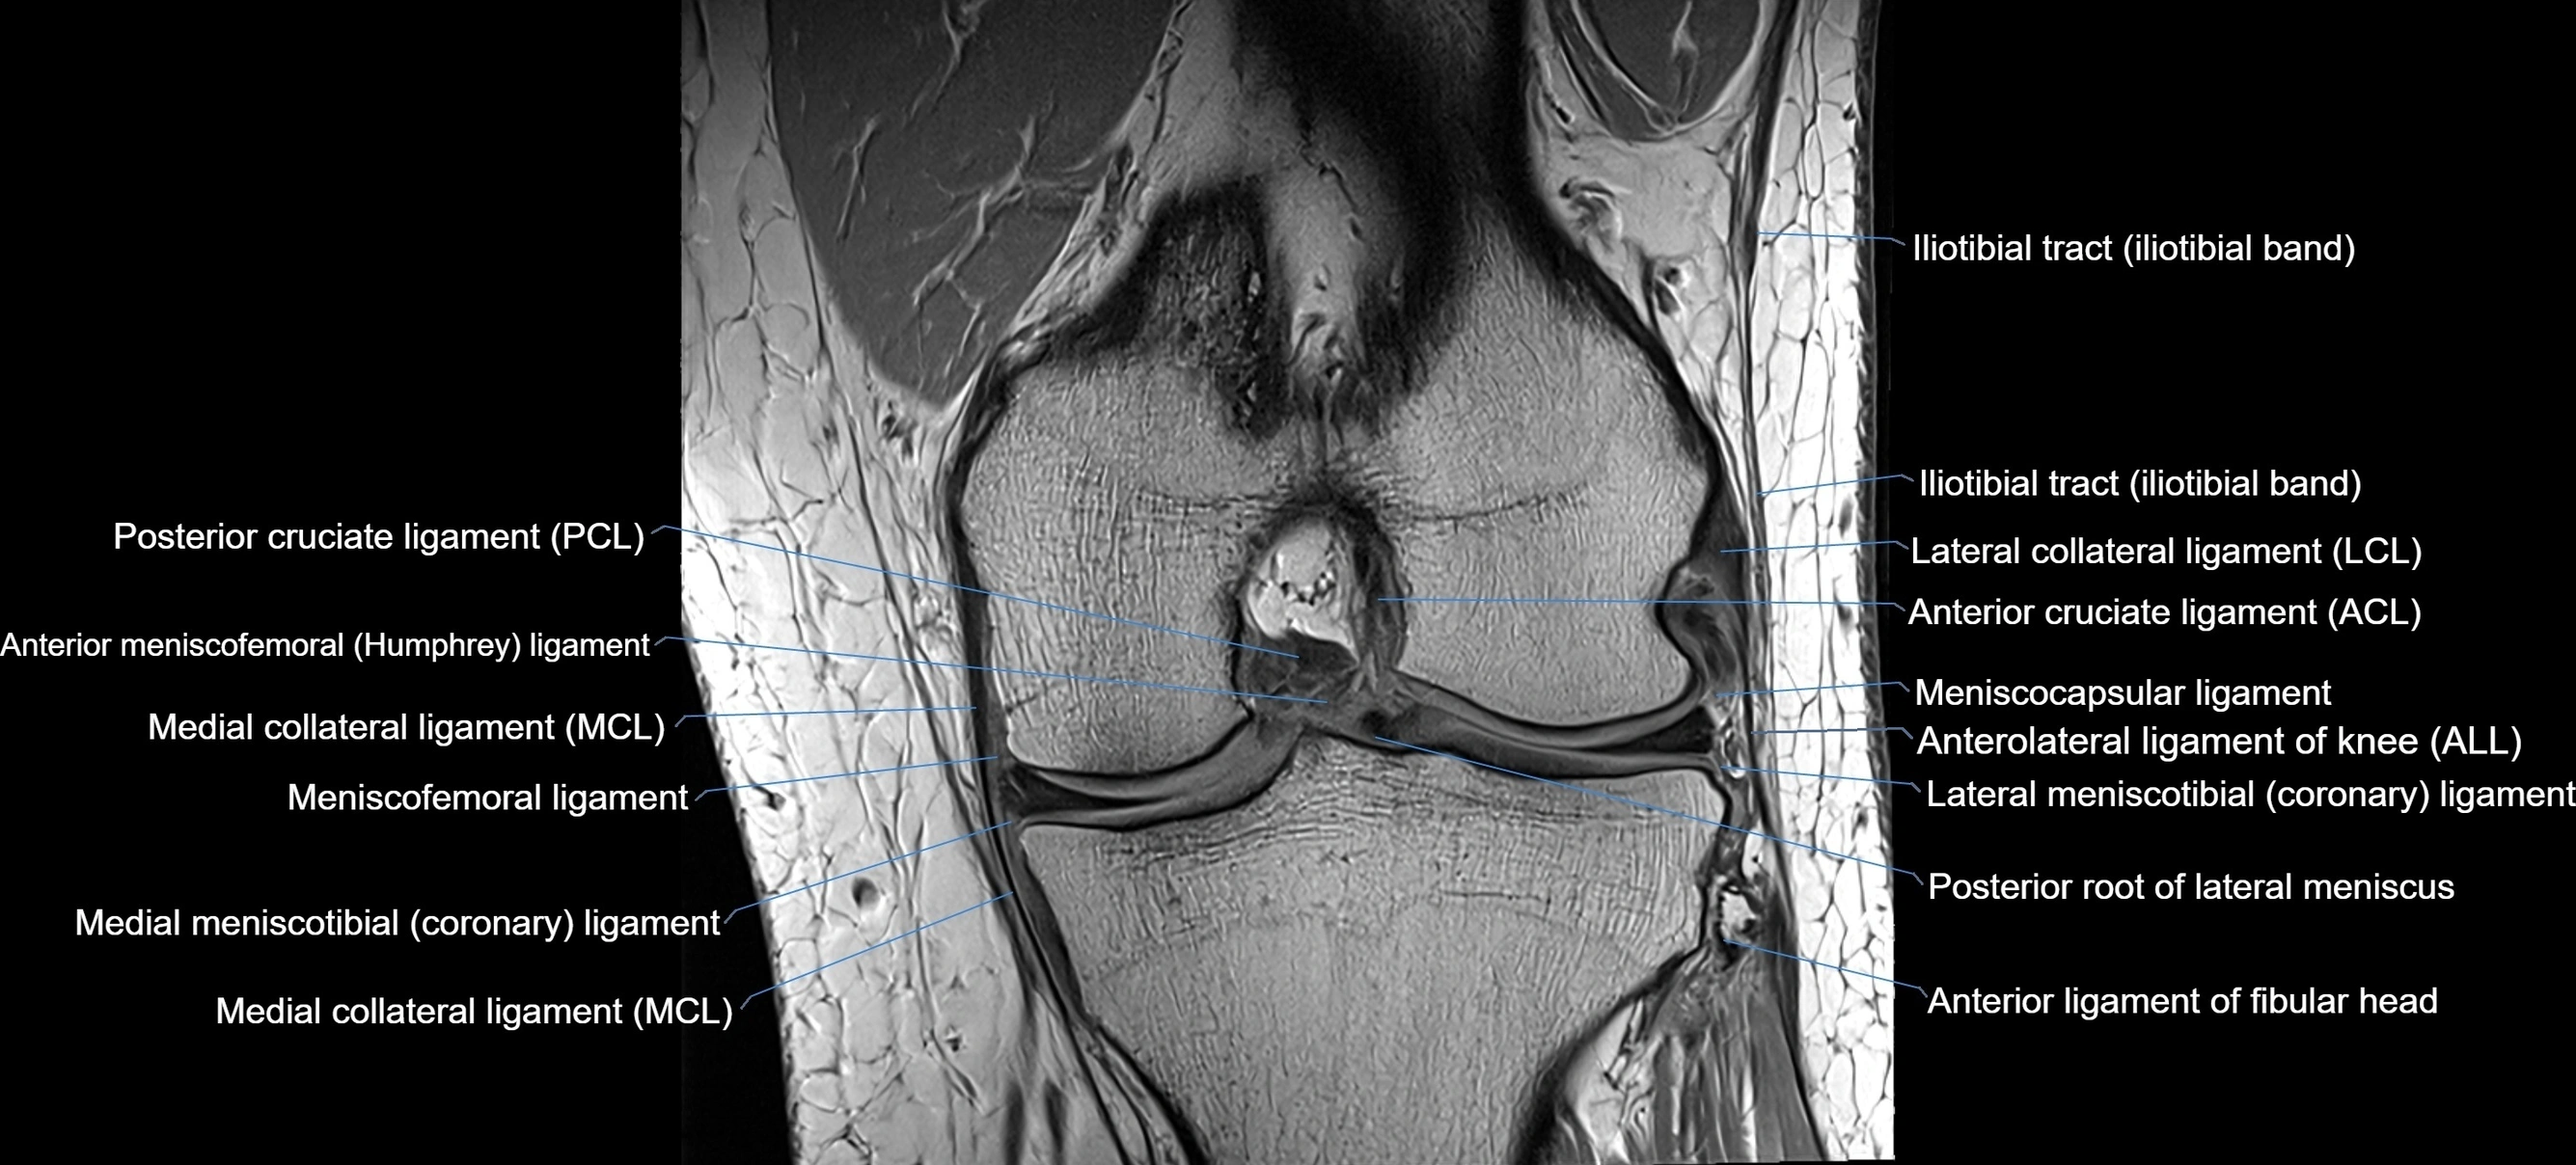

MRI Appearance

T1-weighted images:

• Normal ACL appears as a low-signal band-like structure crossing the intercondylar notch

• Surrounded by intermediate signal synovial fluid and fat planes

T2-weighted images:

• Normal ACL remains low signal

• Partial or complete tears appear as discontinuity, increased signal, or fiber laxity

STIR (Short Tau Inversion Recovery):

• Normal ACL shows dark low signal

• Acute injury shows bright hyperintensity due to edema and hemorrhage

Proton Density Fat-Saturated (PD FS):

• Normal ACL: dark, low-signal band

• Tears: bright intraligamentous hyperintensity, discontinuity, or abnormal course